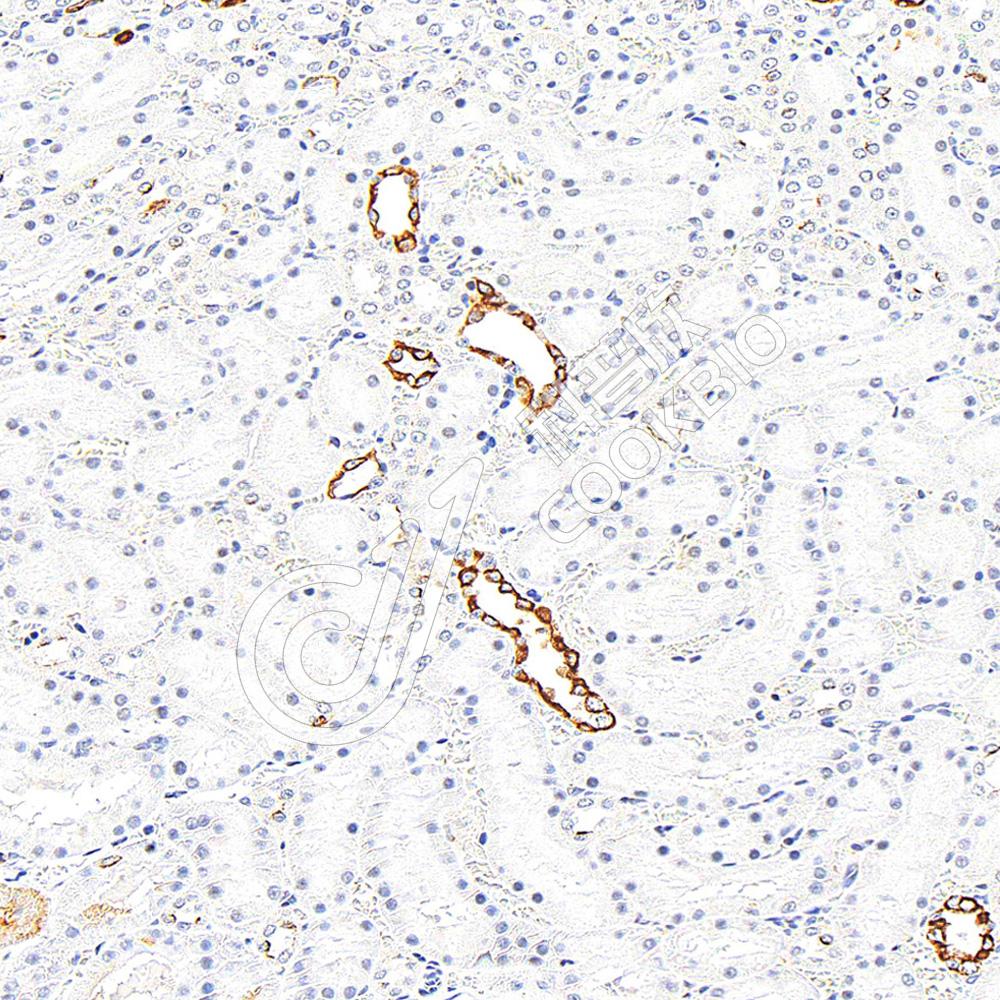

IHC检测Cytokeratin 7蛋白(货号 K1347085).

样品: 人肾, 4%多聚甲醛 (货号KSG1101) 固定12-24小时.

抗原修复: 柠檬酸抗原修复液(干粉, pH 6.0) (KSG1201), 98℃, 20分钟.

—抗: 1: 800稀释, 4℃ 孵育过夜.

二抗: S-vision免疫组化多聚二抗(山羊抗兔),即用型 (货号KB3906), 室温孵育20分钟.

样品: 大鼠肾, 4%多聚甲醛 (货号KSG1101) 固定12-24小时.